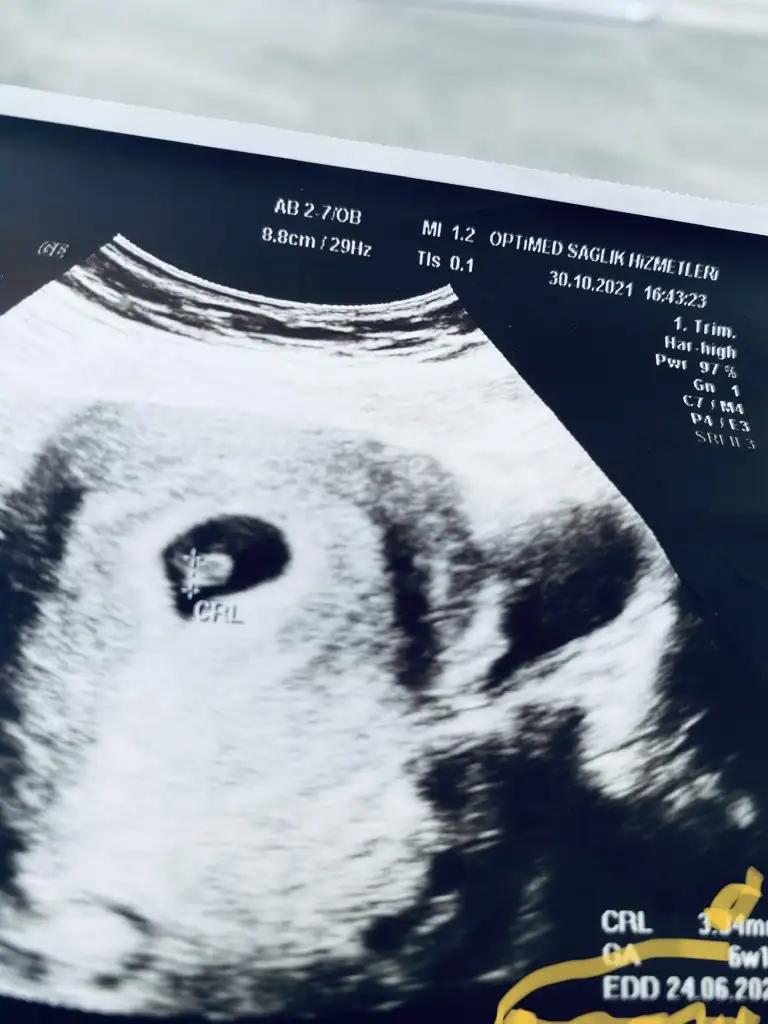

Canım banada bi el atsana bakalım ne olacak tahminin soldaki 6+1 sağdaki 7+6hangisini beğenirsen🤭

• 191BD17C-5B1D-4869-86F2-325ABD1CBCC0.webp

191BD17C-5B1D-4869-86F2-325ABD1CBCC0.webp

35,6 KB · Görüntüleme: 48

• 8CB25C8F-EEB0-4537-9FDF-561D87204538.webp

8CB25C8F-EEB0-4537-9FDF-561D87204538.webp

19,1 KB · Görüntüleme: 47

Evet canım bakalım hayırlısı 🥰